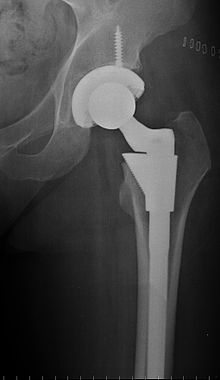

Τα τελευταία χρόνια δυναμικά στο προσκήνιο μπαίνουν οι εγχειρήσεις μικρής επεμβατικότητας, δηλαδή με μικρές τομές και προσπελάσεις. Η ΑΜΙS (αρθοπλαστική μικρής επεμβατικότητας) είναι μέθοδος με πολύ μικρή τομή ( μικρότερη των 10 εκατοστών) χωρίς τομή μυών ή τενόντων όπως στην κλασσική επέμβαση. Έτσι η μετεγχειρητική νοσηλεία είναι πολύ ελαφρύτερη, με σπάνιες επιπλοκές, ελάχιστες μεταγγίσεις και πολύ γρήγορη κινητοποίηση, από την 2η ημέρα.

Η ΑΜΙS είναι εξαιρετική επιλογή στη θεραπεία οστεοαρθρίτιδας του ισχίου, δεν μπορεί όμως να εφαρμοστεί σε όλους τους ασθενείς (σωματότυπος). Απαιτεί ειδικά εργαλεία κι εκπαιδευμένη στη μέθοδο χειρουργική ομάδα.